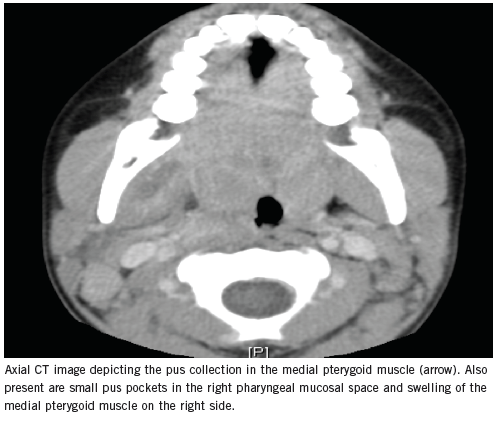

Usha Sethuraman, MD; Rajkumar Agarwal, MD

A 7-year-old boy presented to the emergency department with pain and swelling of the right side of his face and difficulty in opening his mouth.